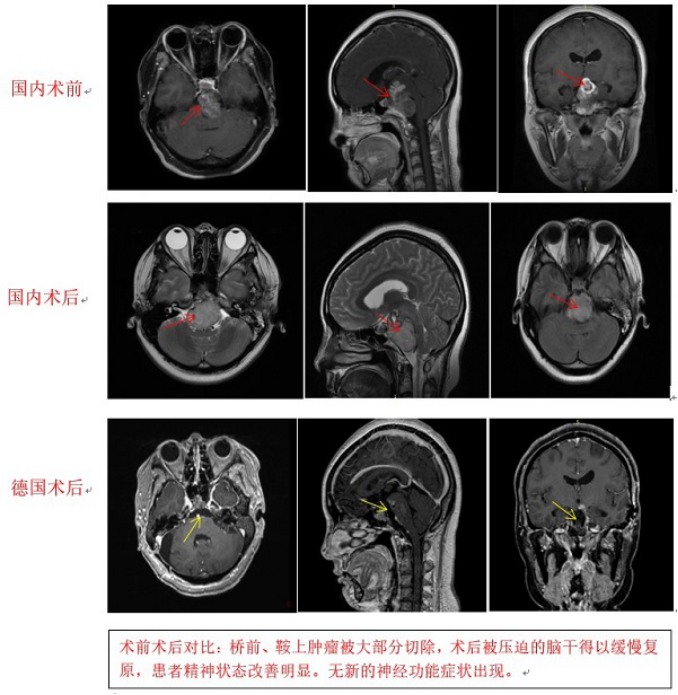

【脊索瘤案例】年仅22岁的95后小姑娘雯雯(化名)怎么也没想到,自己持续3个月的头痛、头晕、耳鸣一经检查就是“桥前斜坡脊索瘤”,颅内比较少见的一种...

相信在生活中,都基本出现过头痛、头晕、耳鸣这些生活中比较常见的症状,但是年仅22岁的95后小姑娘雯雯(化名)却因头痛、头晕、耳鸣被查出桥前斜坡脊...